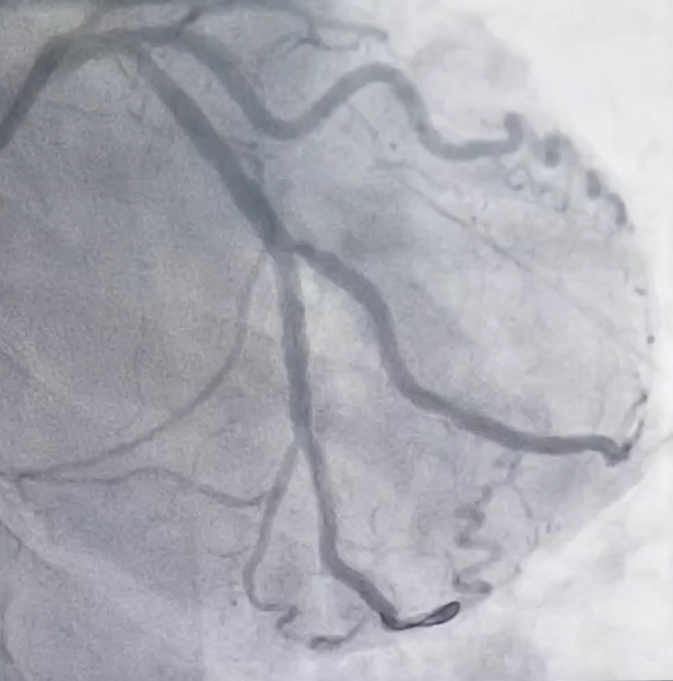

![]() |

| Tắc hoàn toàn động mạch liên thất trước bên trái Mạch tuần hoàn bàng hệ từ động mạch vành phải sang nuôi động mạch vành trái |

Sau khi hội chẩn, các bác sĩ Khoa Can thiệp Tim và mạch máu đã thống nhất tiến hành can thiệp đặt stent động mạch vành cho người bệnh. Sau 2 lần thực hiện phương pháp can thiệp động mạch vành, các bác sĩ đã tái thông và đặt stent 2 nhánh mạch lớn là động mạch vành phải và động mạch mũ bên trái. Sau can thiệp 5 ngày tình trạng của người bệnh ổn định, có thể tự đi bộ, leo cầu thang và không còn những cơn đau ngực khi gắng sức. Người bệnh đã được xuất viện và tái khám định kỳ.

| Động mạch vành phải sau can thiệp đặt stent Động mạch mũ sau can thiệp đặt stent |